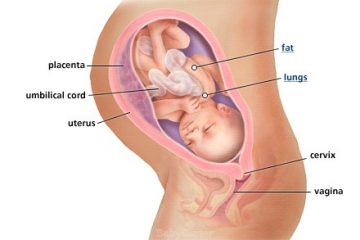

Đã bao giờ chị em muốn biết bé yêu của mình lớn từng ngày trong bụng mình như thế nào không? Hãy cùng chúng tôi khám phá những ...